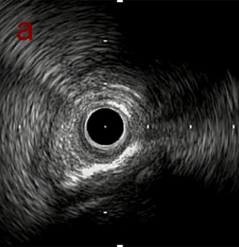

IVUS imaging

IVUSでは8時方向からPD枝がはいいてくる。

PreのIVUSではaの部位のみlipid plaqueを認め削ることでdistal embolismのリスクがあり、そのほかは270度の偏心性石灰化であるがwire biasは良好。